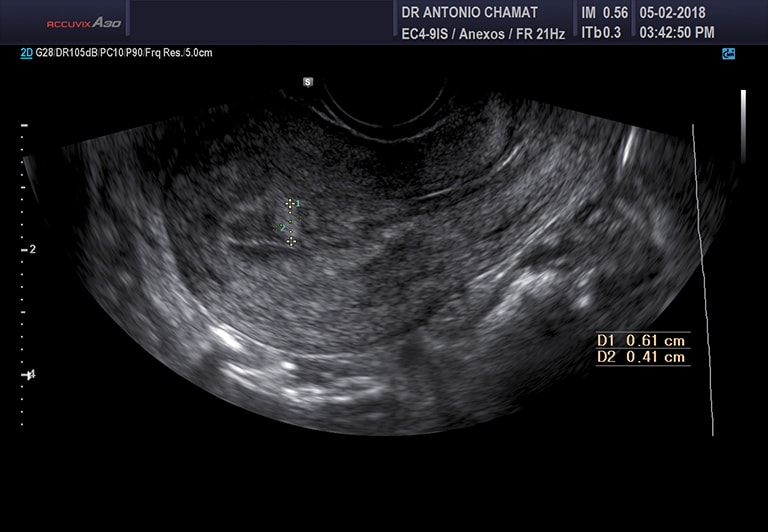

Foliculograma

Es un seguimiento ecográfico por vía transvaginal (3 ó 4 ecografías en total) con el objetivo de encontrar la fecha de ovulación y así determinar los días fértiles. Este estudio es útil en parejas con problemas de fertilidad y en mujeres con trastorno de la ovulación.